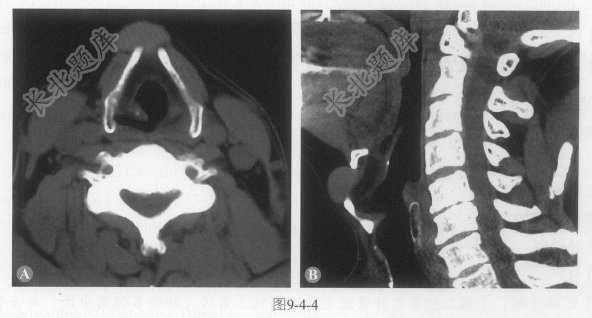

[材料题] 患者男性,68岁,2周前无明显诱因发现上颈部正中肿物,无特殊不适。可随吞咽运动上下活动。CT图像如图9-4-4,平扫CT值约70HU。

单项选择题4.最可能的诊断是:

A、鳃裂囊肿

B、甲状舌管囊肿

C、血管畸形

D、表皮样囊肿

E、神经鞘瘤